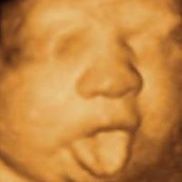

Baby Expressions 3d 4d Ultrasound In The City Colorado Springs

Baby Expressions 3d 4d Ultrasound Colorado Springs Alignable

Baby Expressions 3d 4d Ultrasound Closed 30 Photos 12 Reviews Ultrasound Imaging Centers 814 S Tejon St Colorado Springs Co Phone Number Services

Colorado Springs 3d 4d Hd Ultrasound Enso Prenatal

The Differences Between 2d 3d And 4d Ultrasounds Explained Focus On The Family